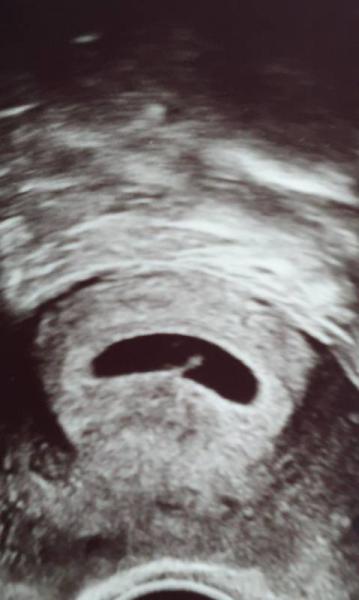

Heute hatten wir unser erstes Ultraschall bei 5+4 Man konnte ein Embryo mit Herzschlag sehen Wir sind so glücklich über unser Krümelchen :) Könnte den ganzen Tag vor Glück weinen!

Bild zu Hallo krümelchen - Forum für Juli - Mamis